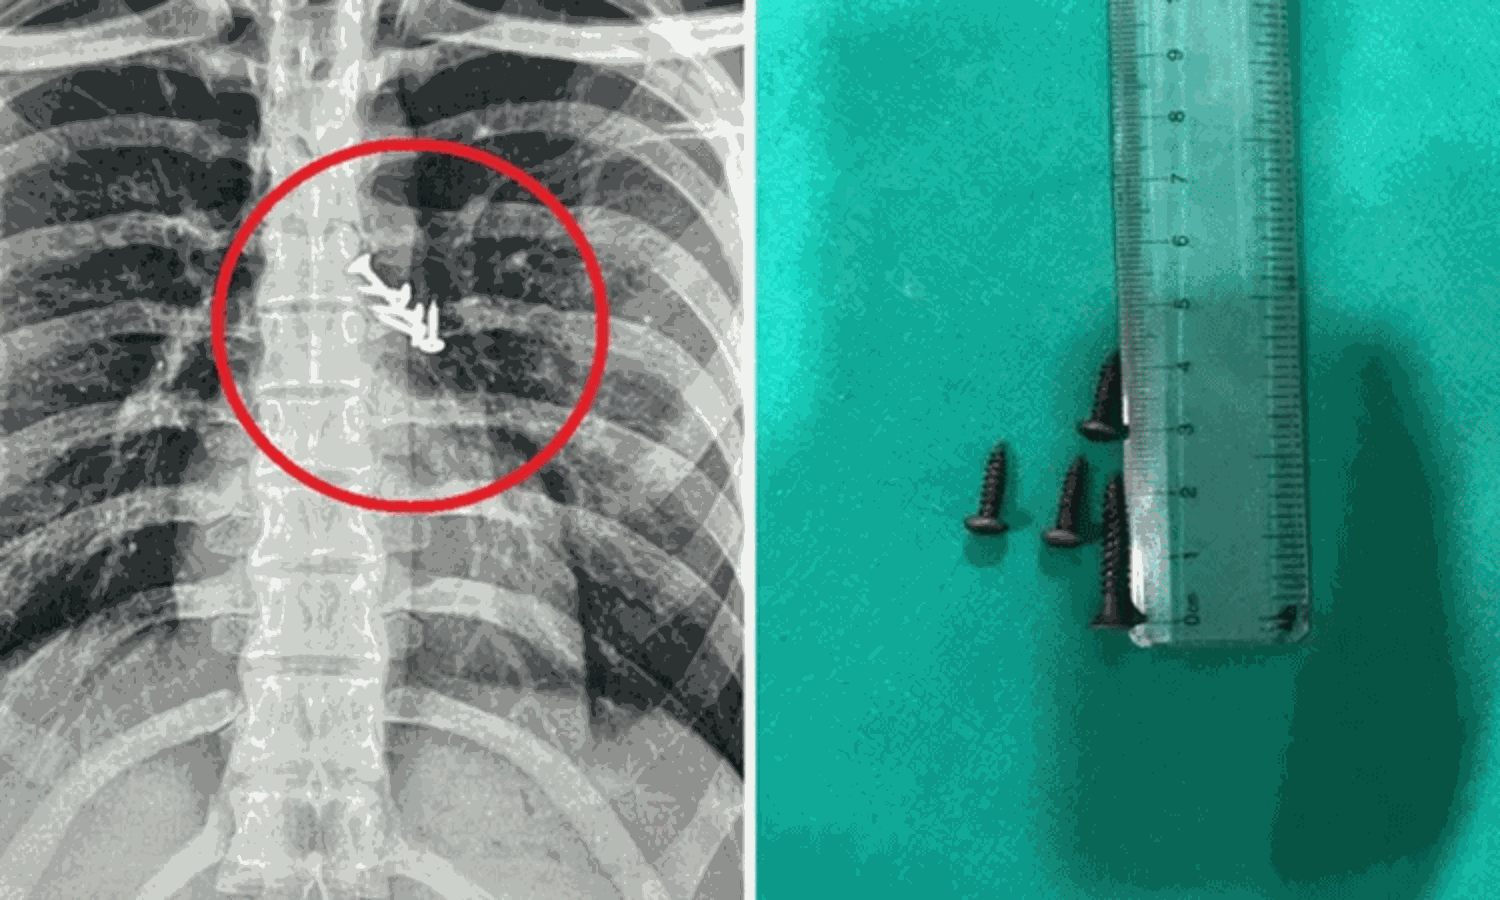

மகாராஷ்டிரா மாநிலம் பிம்பிரி மருத்துவமனையில், உறங்கிக்கொண்டிருந்த இளைஞர் தவறுதலாக விழுந்த ஆணிகளை விழுங்கிவிட்டதாக கூறி சிகிச்சைக்கு அனுமதி செய்யப்பட்டார். மருத்துவர்கள் ஸ்கேன் செய்தபோது நுரையீரல் மற்றும் வயிறு பகுதியில் ஆணிகள் இருந்தது.

உடனடியாக சுமார் 3 மணிநேர அறுவை சிகிச்சை செய்யப்பட்டு ஆணிகள் வெளியே எடுக்கப்பட்டன. இதனால் 19 வயது இளைஞரின் உயிர் காப்பாற்றப்பட்டது. மருத்துவ குழுவினருக்கு இளைஞரின் பெற்றோர் நன்றியை தெரிவித்துக்கொண்டனர்.